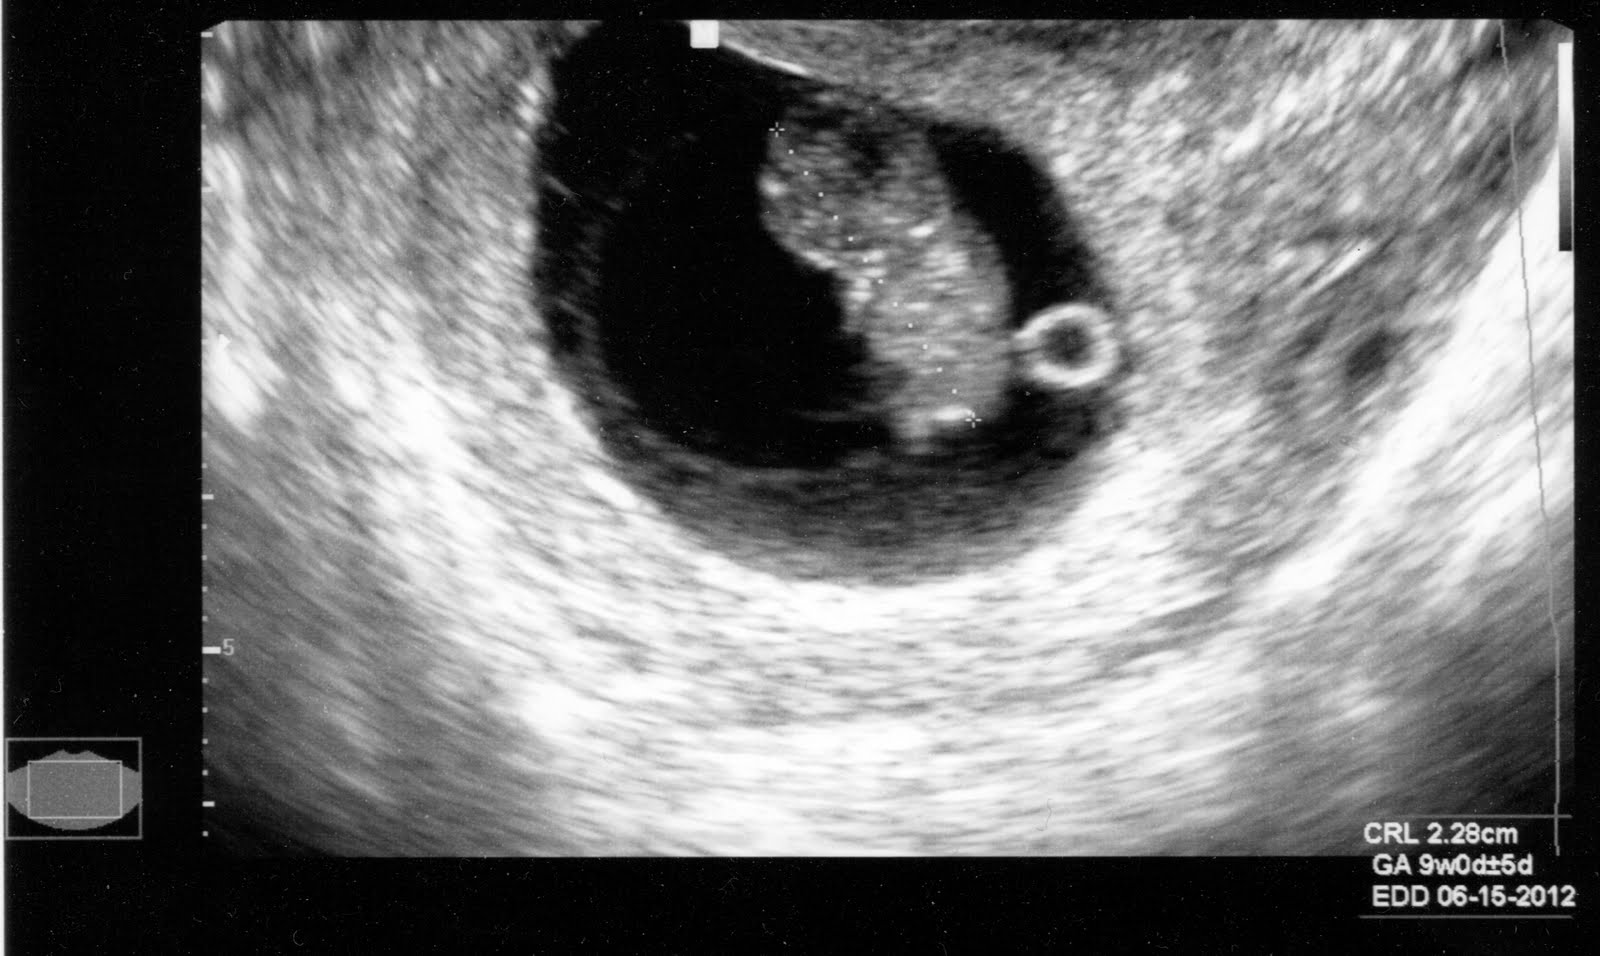

Эмбрион 6 7 Недель ФотоВыберите Ваш пол👨 👉🏻👉🏻👉🏻МУЖЧИНА👈🏻👈🏻👈🏻👩🦱 👉🏻👉🏻👉🏻ЖЕНЩИНА👈🏻👈🏻👈🏻Эмбрион 6 7 Недель Фото (132 фото)